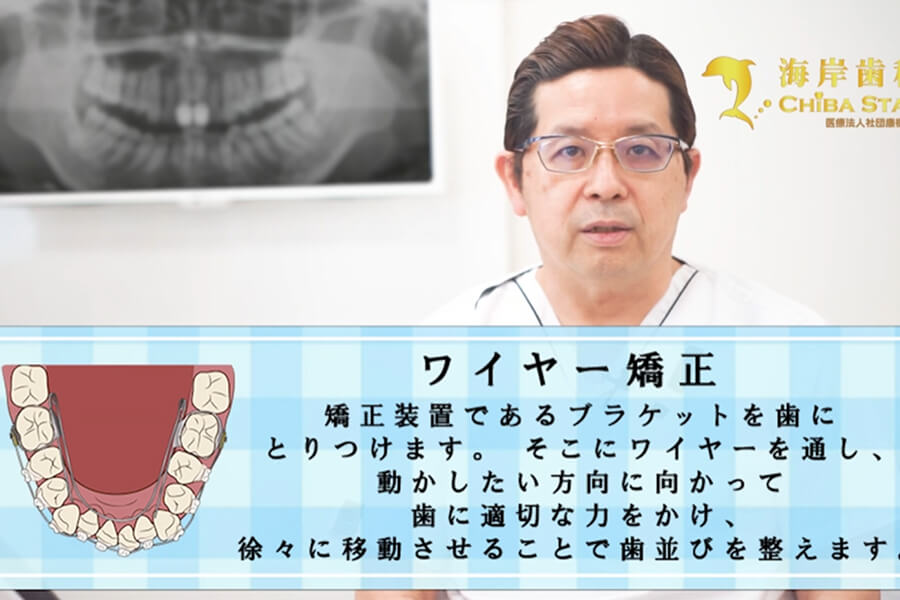

当院では、インビザラインを用いたマウスピース矯正をメインとして行っております。 マウスピース矯正での治療が困難で、ワイヤー矯正が必要な方の場合、ワイヤー矯正に知見を持った先生を紹介し、受診のフォローをさせていただいております。